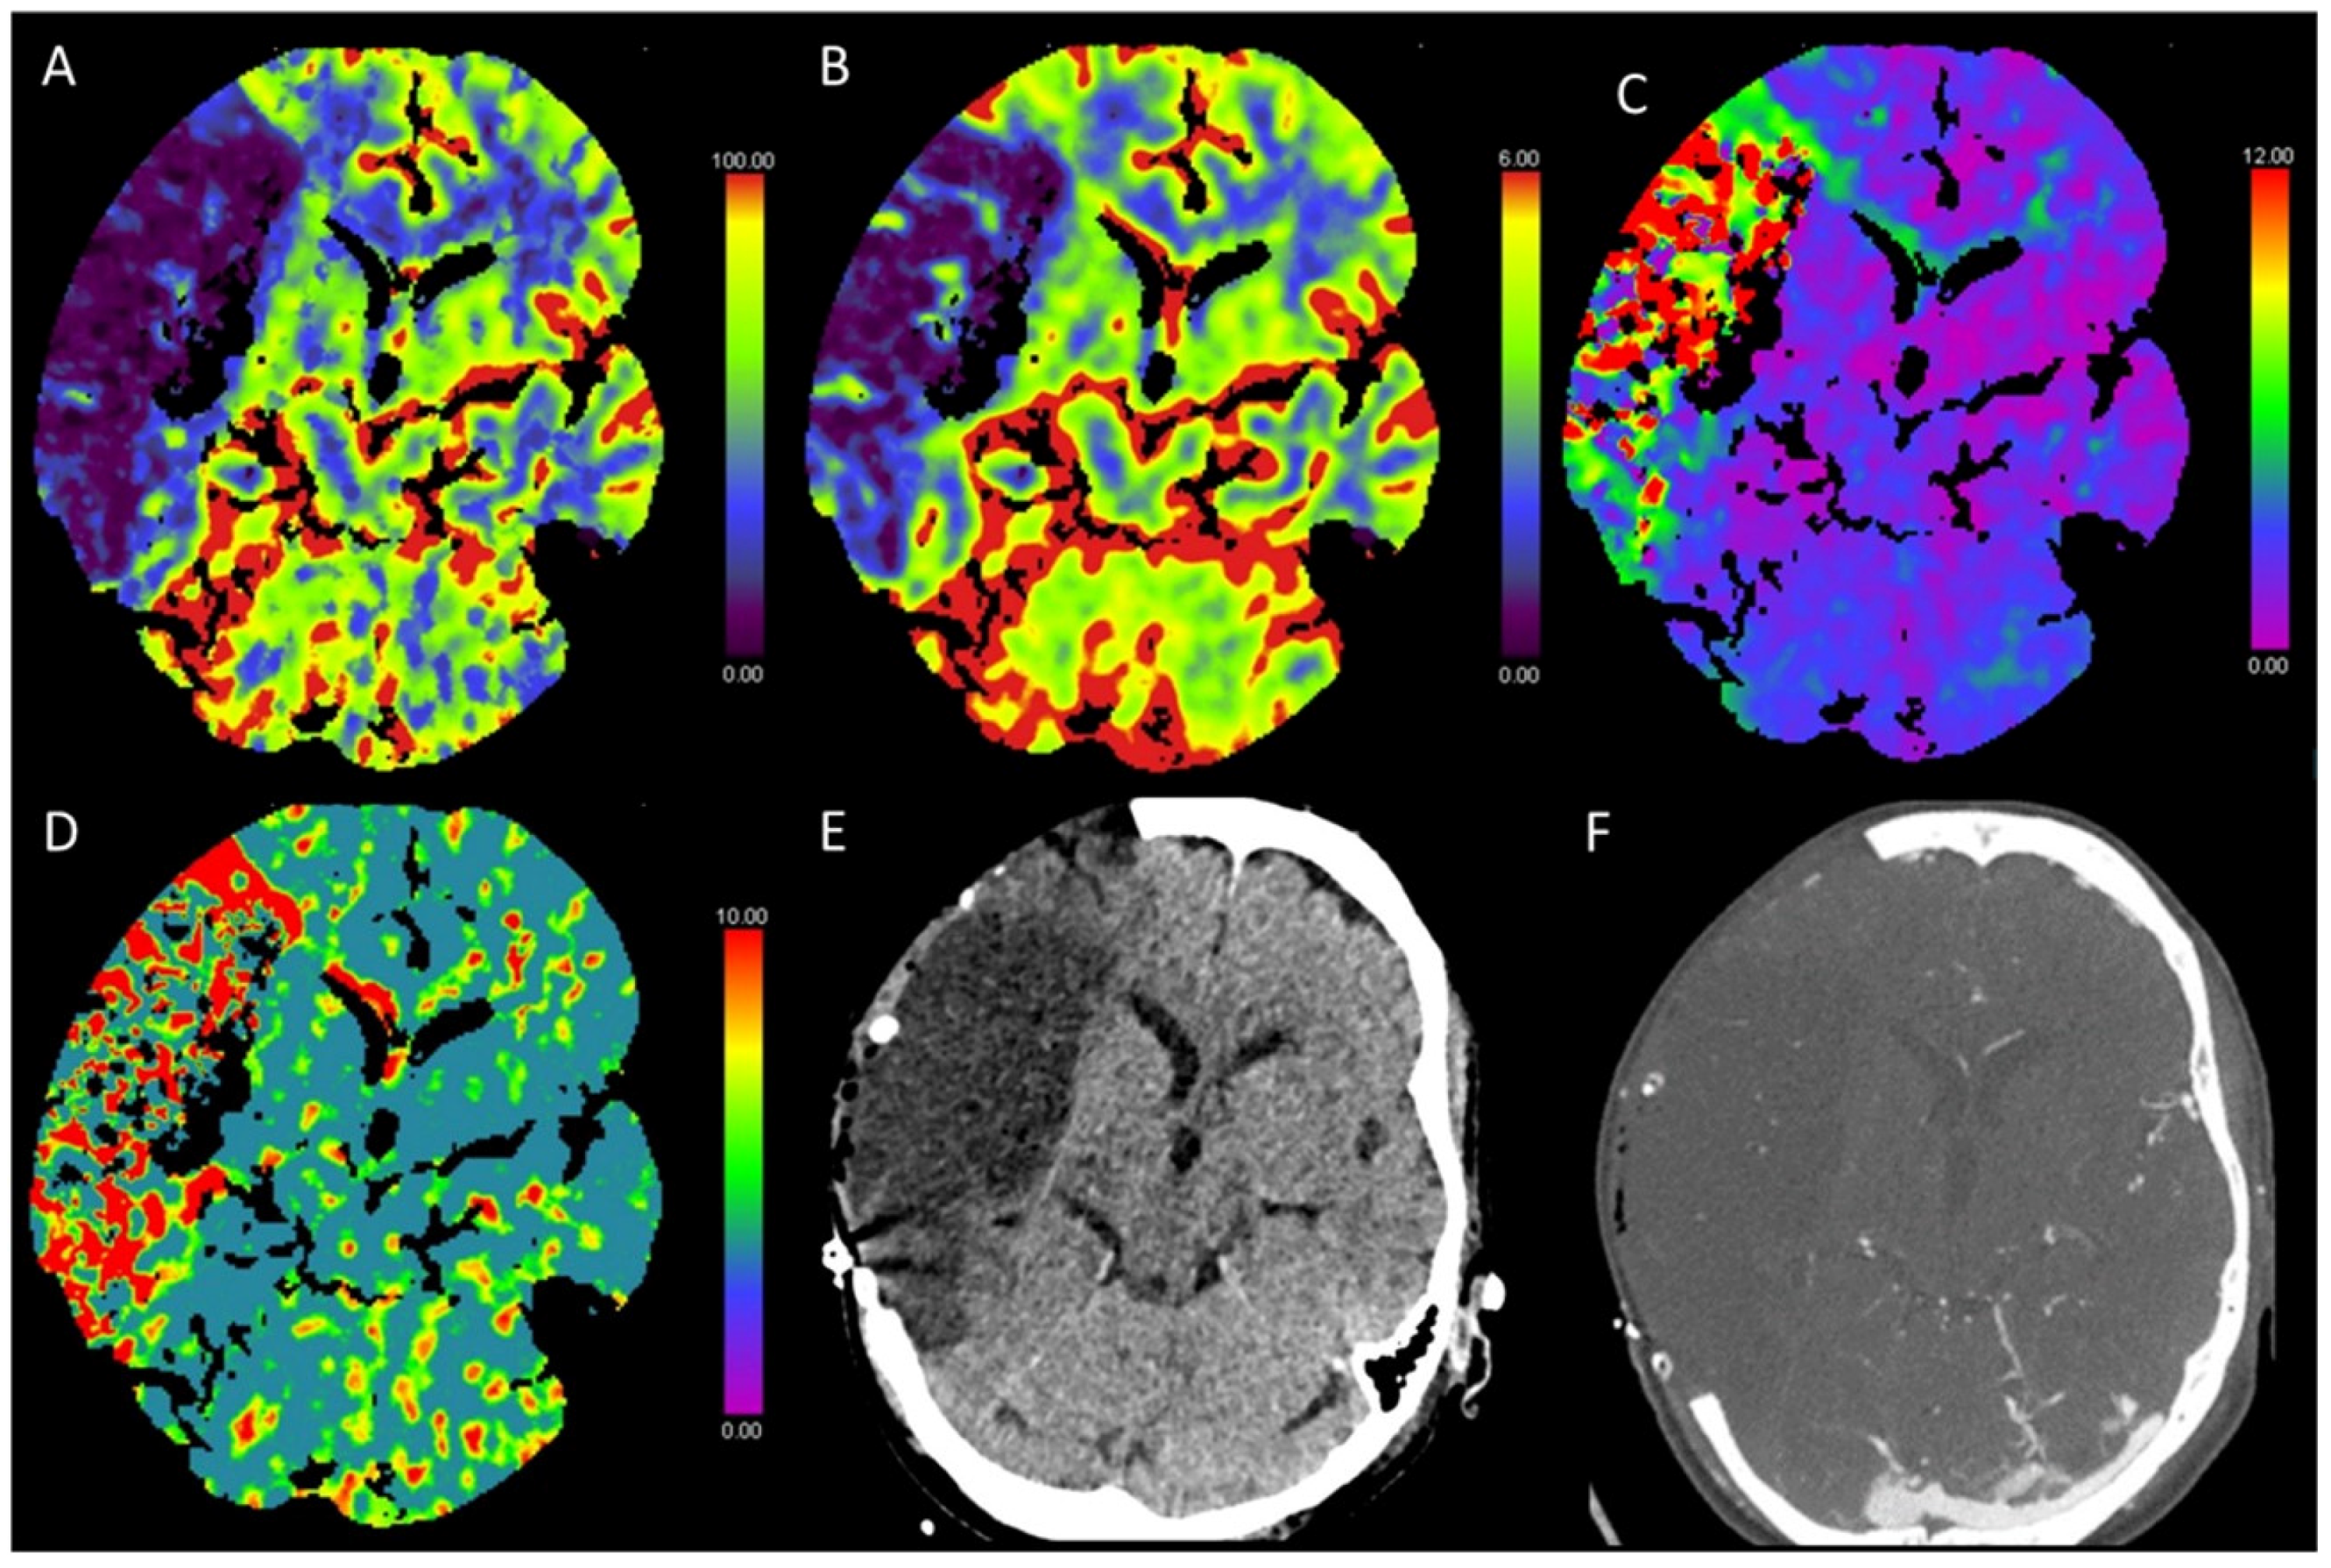

3.10. Postictal Stroke Mimics